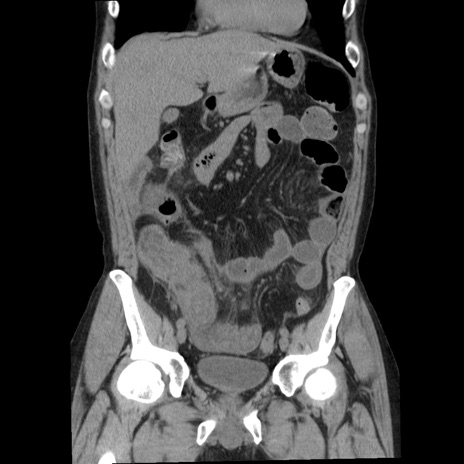

症例29(冠状断像)

【症例】40歳代男性

【現病歴】2日前から胃痛あり。徐々に周期的な激痛に変化した。本日になっても激痛があるため受診。

【身体所見】意識清明、BT 38-39℃台あり、腹部:膨満、やや硬、右下腹部に圧痛あり。

【データ】WBC 8500、CRP 23.26